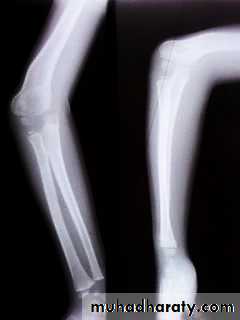

QUIZ

1)What do we call this deformity?2)What is the main causes for such a deformity ?

DiagnosisCubitus varus is not able to be diagnosed until healing of the prior fracture, as the arm must be in full extension, not in flexion, for the deformity to be noticed